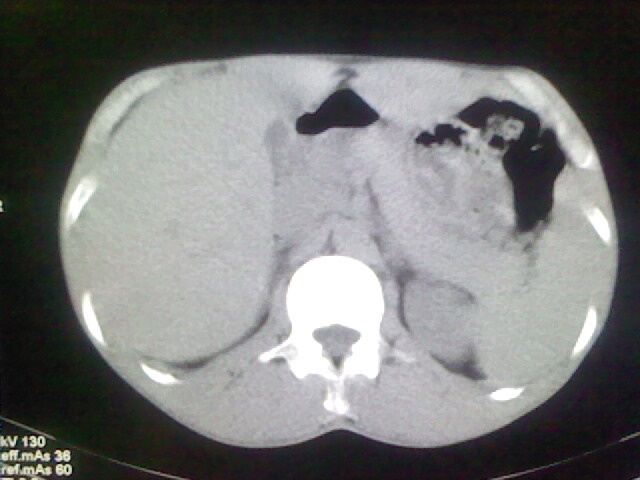

以下是引用杀毒软件在2008-9-3 6:11:00的发言:[br]侵袭性胸腺瘤------一般不侵到气管旁[br][br]考虑----纵隔淋巴瘤,心包及胸膜受累

以下是引用随光逐影在2008-9-3 7:07:00的发言:[br]1)考虑淋巴瘤可能。2)双侧胸腔积液(以左侧为甚)。3)心包积液。